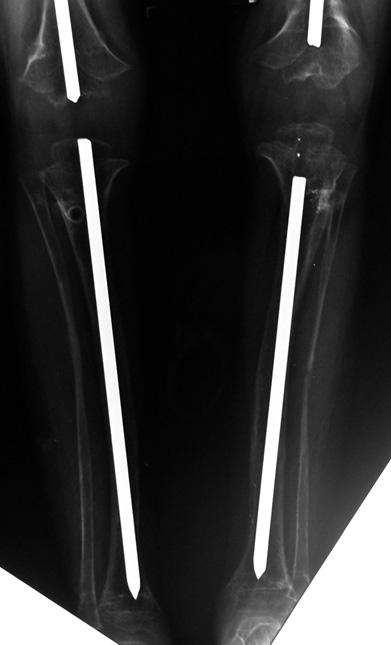

14 ve 16 yaşlar arasında her iki femurda toplam 10-12 cm boy uzatma her iki kalçanın fleksiyon deformitesinin düzeltilmesi (bu lomber hiperlordozu düzeltir) her iki kalçanın varus deformitesini düzeltme ortalama eksternal fiksasyon tedavi süresi = 10-12 ay